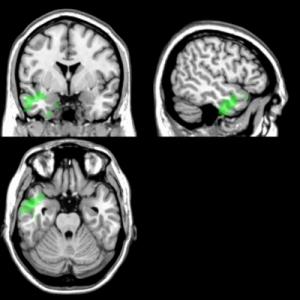

Hsieh y sus colegas estudiaron a 20 sujetos sanos, 12 pacientes con enfermedad de Alzheimer y 11 pacientes que sufren de demencia semántica (DS), una forma menos común de demencia que afecta a conocimiento de los hechos de palabras y conceptos. Los participantes escuchaban fragmentos musicales, que fueron obligados a etiquetar como feliz, tranquilo, triste o que daba miedo, o miraron las fotografías de rostros a los que debían catalogar como triste, feliz, sorprendido, asustado, disgustado o enojado. Los participantes también se sometieron a una resonancia magnética, cuyos resultados se compararon con los resultados de las pruebas de reconocimiento.

Los pacientes con ambos tipos de demencia mostraban problemas en la identificación de emociones en rostros y en la música. Como Hsieh y sus colegas esperaban, el lado derecho y ciertas regiones del cerebro, en particular la amígdala, el lóbulo temporal y la ínsula estaban dañadas; partes que se asocian al reconocimiento de emociones en rostros y en la música.

Pero los investigadores se sorprendieron al descubrir que los lóbulos temporal izquierdo anterior e inferior, que normalmente se asocian con el lenguaje y las habilidades verbales, eran cruciales en el reconocimiento de la emoción en la música también. En otras palabras, reconocer el contenido emocional de una melodía se basa en algunos de los mismos recursos que se utilizan para dar sentido a una frase.